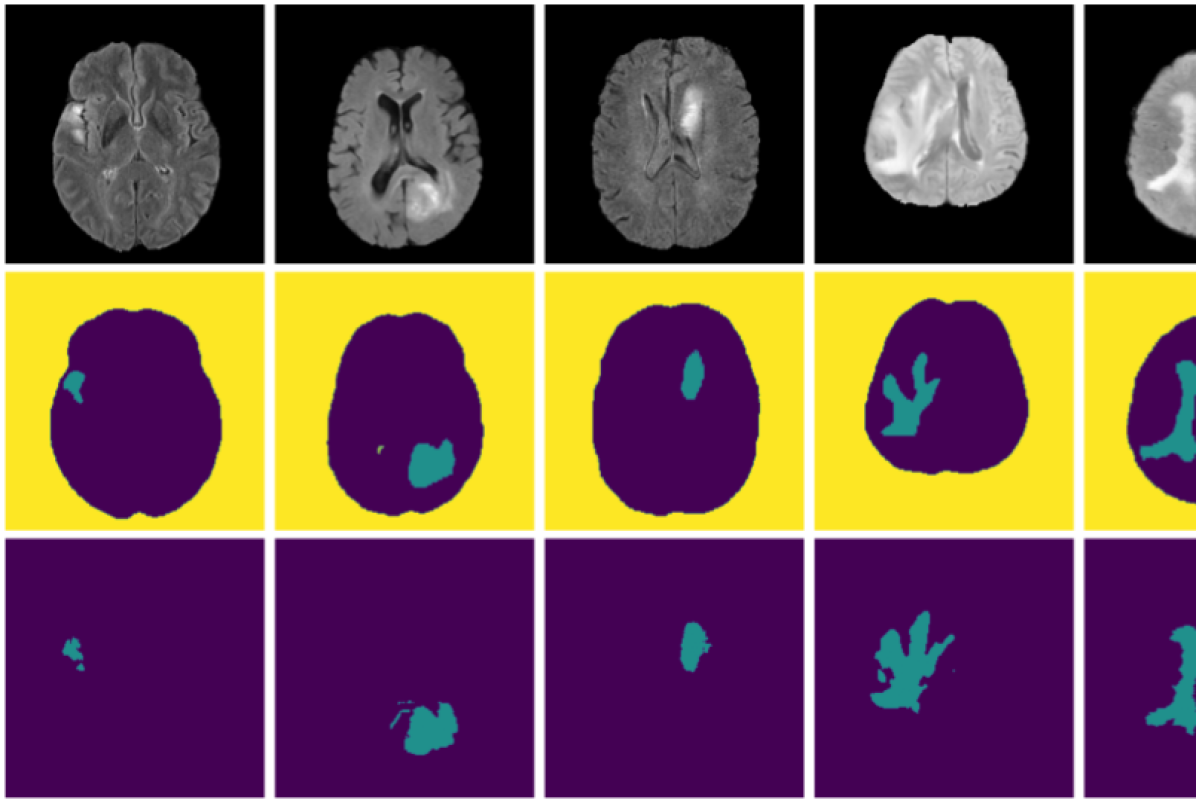

For the Brain Tumor Segmentation (BraTS’19) dataset, we use the whole tumor (WT) segmentation mask for evaluation, which is detectable based on the FLAIR images alone. We train segmentation models with K=3𝐾3K=3 parts (background, brain, tumor). The evaluation metric, as in the BraTS’19 challenge [21], is Dice score and the 959595th percentile of the symmetric Hausdorff distance, which quantifies the surface distance of the predicted segmentation from the manual tumor segmentation in millimeters. Tab. 3 shows that our model outperforms all prior unsupervised methods for both evaluation metrics. As an approximate upper bound we show for reference the reported results of the 1st1𝑠𝑡1st place solution [17] on BraTS’19 which is based on supervised training on the full train set and evaluated on the BraTS’19 test set. The qualitative results in Fig. 4 show that our model can detect tumors of different sizes. Our predictions look smoother and do not capture fine details of tumor segmentations.

Refer to caption

Sample Slice

Discovery

Manual Seg.

Figure 4: Examples of discovered structures on BraTS’19. Our method discovers meaningful regions and detects tumors of different sizes in an unsupervised manner.